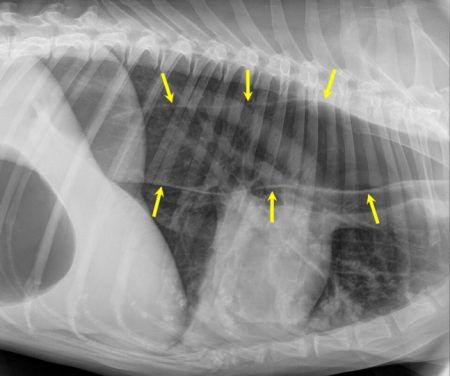

【코코타임즈】 음식엔 별다른 이상이 없는데도 자주 토하는 개에겐 '거대식도증'(megaesophagus)이란 병이 있을 수 있다. 식도에 들어간 음식물을 위로 보내지 못해 식도가 부풀면서 커져 보이는 병이다.

미국 워싱턴주립대(WSU) 수의대 수잔 메하인(Susan Mehain) 박사와 사라 게스(Sarah Guess)는 거대식도증을 앓는 개 10마리에게 실데나필을 2주 동안 투여하는 실험을 진행했다. 비디오 형광투시법을 사용해 음식물이 식도를 따라 이동하는 경로도 관찰했다.